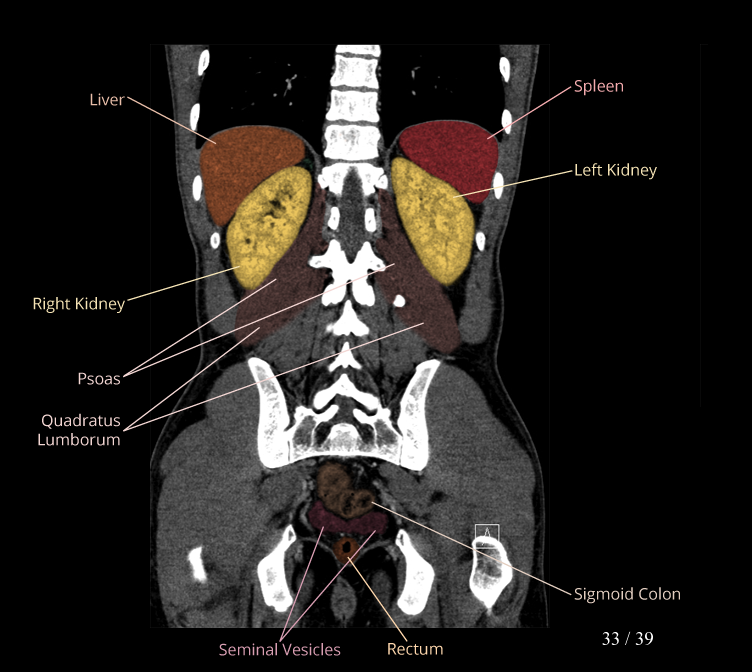

Body

Covers abdominal CT anatomy.